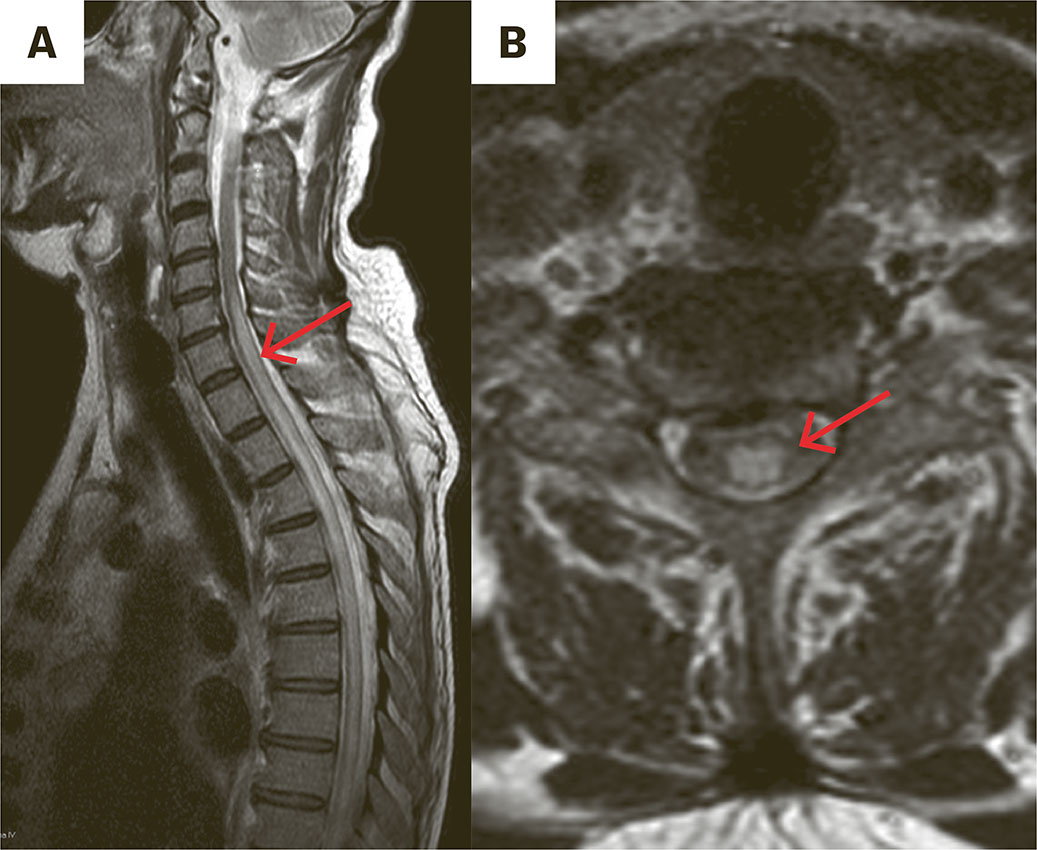

Samme dag varslet sykepleier om at pasienten ikke klarte å stå på beina. Ved klinisk undersøkelse fant man akutte pareser (kraftgrad 1–2) i begge underekstremitetene, sensibilitetsforstyrrelse fra L2-nivå bilateralt og bortfall av sfinktertonus. Han hadde utslukket patella- og akillesreflekser og nedadvendte plantarreflekser. På mistanke om intraspinal blødning ble det gjort MR totalkolumna som viste økt T2 signal i tilnærmet hele tverrsnittet av medulla fra C7-nivå til conus. Differensialdiagnostiske overveielser inkluderte myelitt, spinal iskemi og dural arteriovenøs fistel. Dalteparin ble nullet og spinalpunksjon utført dag 13. Gjennom det neste døgnet utviklet mannen komplett tverrsnittslesjon i Th3-nivå. Ny MR totalkolumna, nå med kontrast, viste økende utbredelse av de intramedullære forandringene, uten patologisk kontrastopptak eller restriktiv diffusjon, mest passende med myelitt (figur 1).